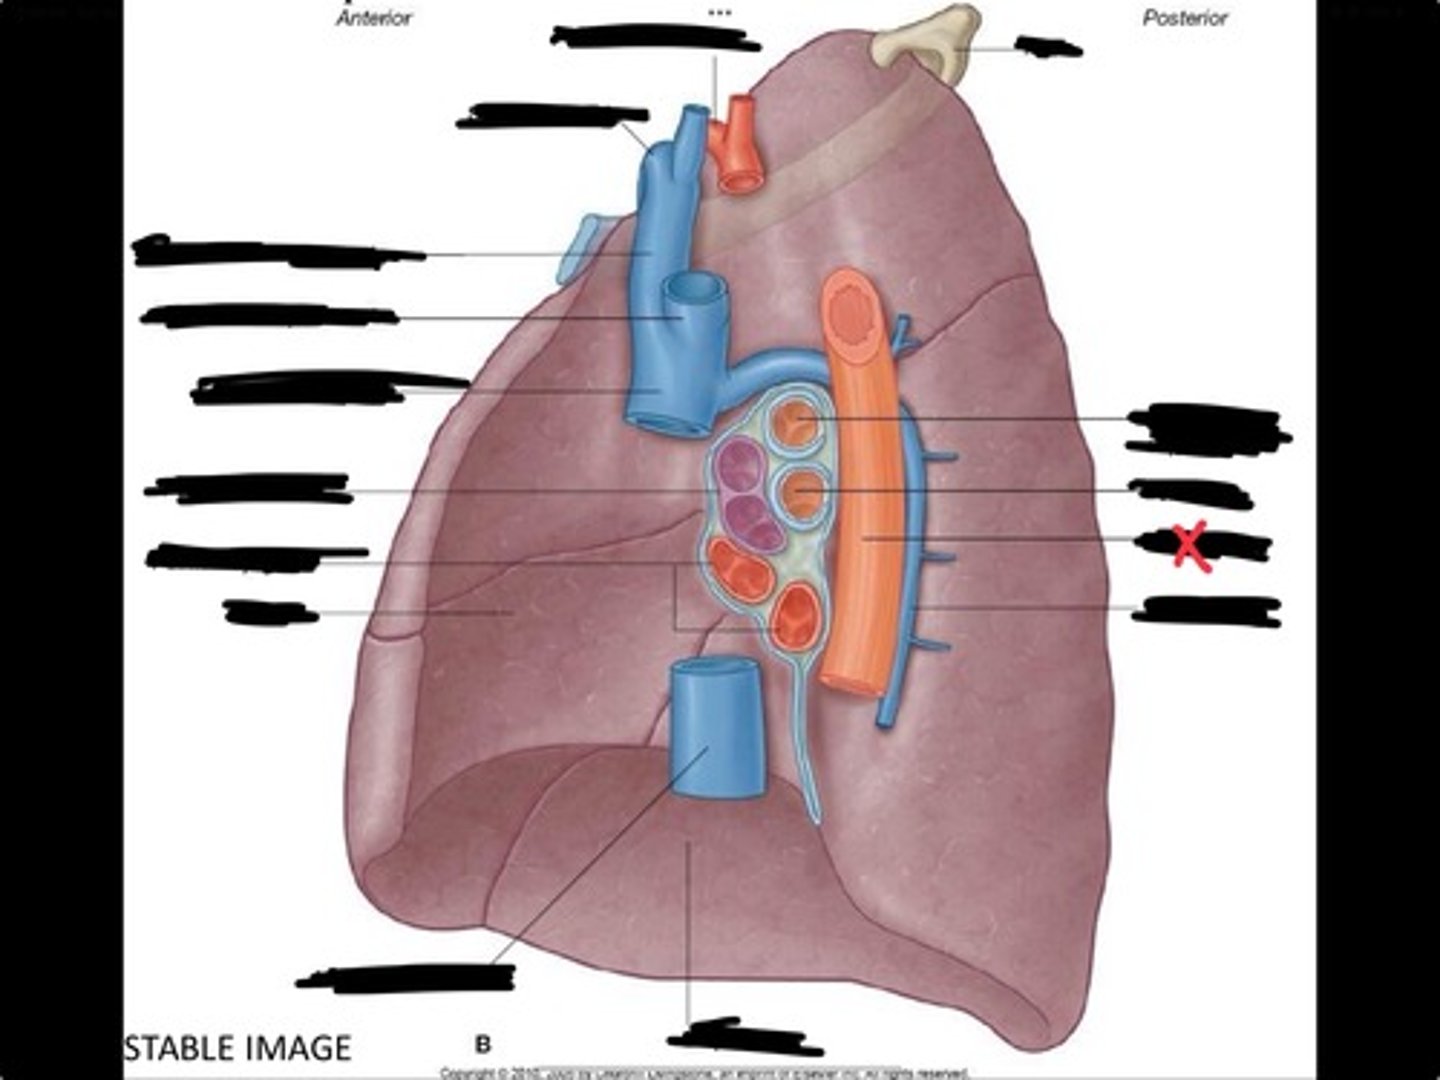

Diaphragm

Inferior vena cava

Superior vena cava

Subclavian vein

Right bracheocephalic vein

Subclavian artery

Esophagus

Bronchus

Rib 1

Left subclavian artery

Left brachiocephalic vein

Aortic arch

Pulmonary artery

Pulmonary vein

Heart

Left brachiocephalic vein

Azygos vein

Esophagus

Bronchus

Fibrous pericardium

Parietal layer of serous pericardium

Pericardial cavity

Visceral layer of serous pericardium

Junction between fibrous pericardium and adventitia

Heart

Thoracic aorta

Rib 1

Pulmonary artery

Bronchus to superior lobe